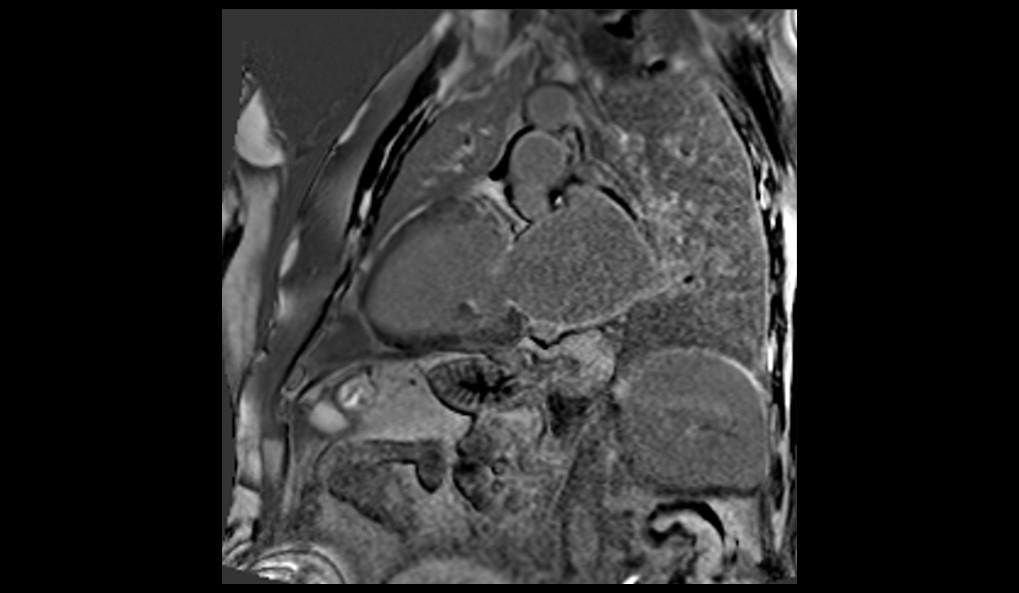

El examen de RMC se realizó en el equipo MAGNETOM Altea 1.5T. Se realizaron secuencias de CINE PSIF, FSE black-blood T1 y T2, phase-contrast, mapeo miocárdico (MyoMaps) T1/T2/T2* y LGE TRUFI high-resolution después de la inyección de contraste (DOTA-Gd 0,5M 0,2mmol/kg).

La RMC evidenció dilatación biatrial importante (AD=170ml/m2 y AE=120ml/m2), dilatación biventricular discreta (VDFVD=115ml/m2 y VDFVE=103ml/m2), FEVD 49%, FEVI 45%, rectificación del septo interventricular, insuficiencia tricúspide moderada, derrame pericárdico discreto, realce tardío heterogéneo en VI de patrones mesocárdico y subendocárdico en segmentos anteriores, anteroseptales, inferoseptales, inferiores y anterolaterales con distribución predominante medio-basal y realce tardío biatrial estadio UTAH IV. El MyoMaps en septo interventricular reveló elevaciones de tiempos T1 nativo (1070ms), T2 (58ms) y del volumen extracelular (33%) con T2* normal (28ms).

Los hallazgos de la RMC son compatibles con el diagnóstico de amiloidosis cardíaca. El patrón de cardiomiopatía dilatada con realce tardío (fibrosis) multisegmentar en VI, evitando segmentos apicales, elevaciones de T1 y VEC y fibrosis biatrial son hallazgos típicos de amiloidosis, especialmente en el subtipo ATTR. La Resonancia Magnética del Corazón, a través de su evaluación multiparamétrica, permite una diferenciación etiológica precisa de las cardiomiopatías, siendo indicada por las mejores guías como examen diagnóstico de primera línea en la investigación de insuficiencia cardíaca.